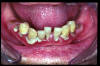

CM Edentulismo parcial. Restos radiculares. Placa bacteriana